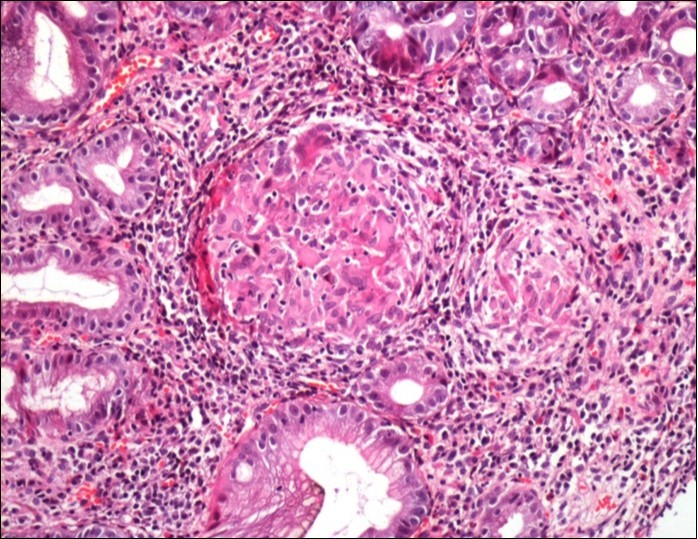

Concerning the etiology, diagnosis was made regarding to the past medical facts, the clinical symptoms, the endoscopic findings and the histological associated lesions. The main etiology was represented by Crohn’s disease in ten cases, followed by gastric tuberculosis in 6 cases. H Pylori was the retained cause of gastric granulomatosis in 5 cases, regarding to the absence of other etiologies, and the favorable issue after antibiotic eradication treatment. In 5 other patients, etiology of gastric granulomatosis was also found and the final diagnosis was a sarcoidosis (n=3), foreign body reaction (n=1), and yersiniosis (n=1). In our series, thirteen cases were unclassifiable despite etiological investigations and no cause of gastric granulomatosis was isolated. Histological findings of a case of tuberculosis and sarcoidosis are represented in Figure 1 and Figure 2.

Figure 2.Histological aspect of gastric granulomatosis secondary to sarcoidosis : Antral biopsy specimens revealing multiple non-necrotizing (sarcoid-like) granulomas ( HEx200)